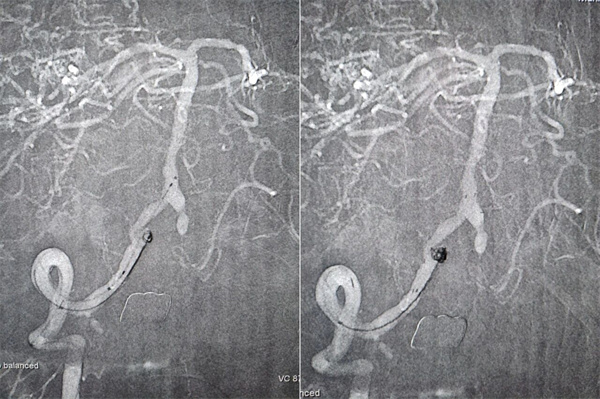

患者高先生,70岁,患有高血压病多年。2年前曾行冠状动脉搭桥术,平素规律服药。2个月前,他因左上肢突然麻木被送至清华大学垂杨柳医院急诊科就诊。头颅CT提示右侧顶叶少量蛛网膜下腔出血。后入住神经外科进一步诊治,全脑血管造影(DSA)结果显示:右侧椎动脉起始部重度狭窄约70%,左侧椎动脉颅内段闭塞;右侧椎动脉颅内段存在大小约3.5×2毫米的夹层动脉瘤;右侧颈内动脉颅外段存在重度狭窄,左侧颈内动脉通过前交通动脉代偿。

▲右侧椎动脉起始重度狭窄,左侧椎动脉颅内段闭塞

▲右侧椎动脉V4段夹层动脉瘤